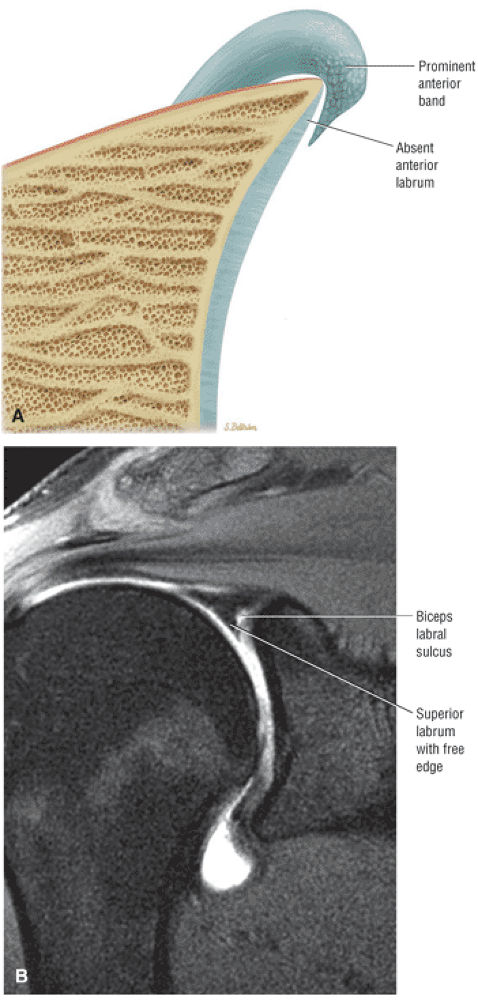

The IGHL contributes to the anterior labrum through its anterior band. The anterior band may be prominent and overlay a small or even absent anterosuperior labrum as a normal variation.

A superior wedge labrum with the labrum firmly attached anteriorly, posteriorly, and inferiorly. Separation (a sublabral foramen) between the glenoid and superior anterior labrum occurs as a normal variation (Fig. 8.62).

A posterior wedge-shaped labrum in which the superior labrum is smaller and more firmly attached to the superior glenoid. The posterior labrum overlaps the articular surface of the glenoid and has a free central border (Fig. 8.63).

An anterior wedge labrum, which is characterized by a large anterior band of the IGHL that replaces or covers a small anterior labrum (e.g., the Buford complex) (Fig. 8.64)

FIGURE 8.62 ● (A) The superior wedge labrum is characterized by a firm attachment of the anterior, posterior, and inferior labrum to the glenoid articular surfaces, with no free central edge. The superior labrum is, however, triangular in cross-section and its central free edge is separated and overlaps the articular cartilage at the biceps labral complex. An associated anterosuperior sublabral foramen is common in this labral type. (B) A superior wedge labrum is shown firmly attached to the anterior and posterior glenoid rim. The anterior band of the IGL blends with the labrum to form one structure near the equator of the anterior glenoid rim. A sublabral foramen may exist in the anterosuperior quadrant in a superior wedge labrum. (C) A superior wedge labrum in which the free central edge of the superior labrum forms the biceps labral sulcus of the biceps labral complex type 2. A sublabral foramen is an associated finding in the anterosuperior quadrant. Note the firm attachment of the anterior labrum (below the equator), posterior labrum, and inferior labrum.

FIGURE 8.64 ● (A) The anterior wedge labrum is firmly attached to the glenoid articular surface inferiorly, posteriorly, and superiorly. The anterior band (AB) of the IGHL, however, is thick and prominent and covers or overlaps the anterior labrum anterior to the anterior glenoid rim. The anterior wedge labrum may be further defined into two subtypes. The first subtype has a small anterior superior labrum, as already described, whereas the second subtype has an absent anterosuperior labrum underneath or deep to the prominent anterior band. Deep to the prominent anterior band of the IGHL, the anterior rim articular cartilage may taper and become thin peripherally. (B) The anterior band of the IGHL overlapping a small anterior labrum. Axial T1-weighted MR arthrogram.